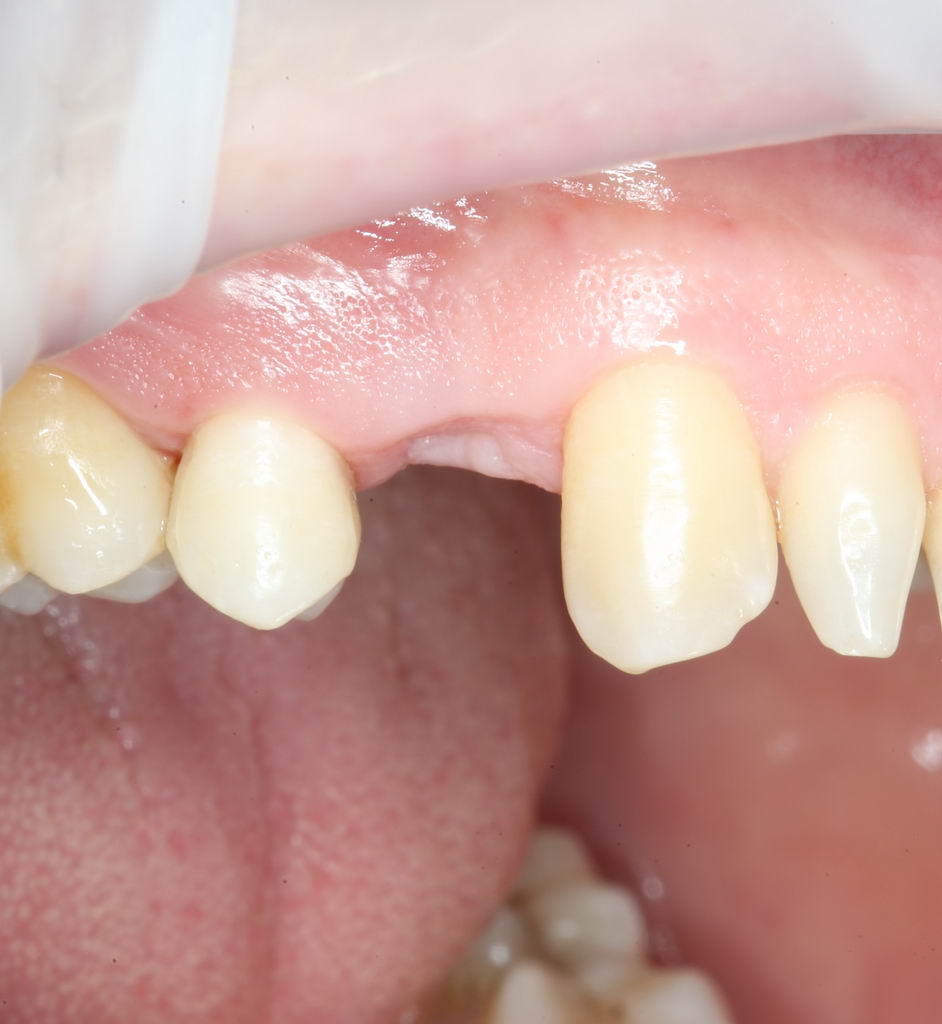

Помните, в самом начале операции мы планировали наложение швов с учётом будущего вестибулярного смещения лоскута? Так вот, теперь у нас есть возможность не просто сместить, но и зафиксировать вестибулярный лоскут. Делается это, так сказать, с подворотом края снаружи:

Обратите снимание, что альвеолярный отросток в этой области стал более объемным. Этого удалось добиться без всяких остеопластических операций или гингивопластики, путём простого перемещения тканей.

Всё. Операция закончена: